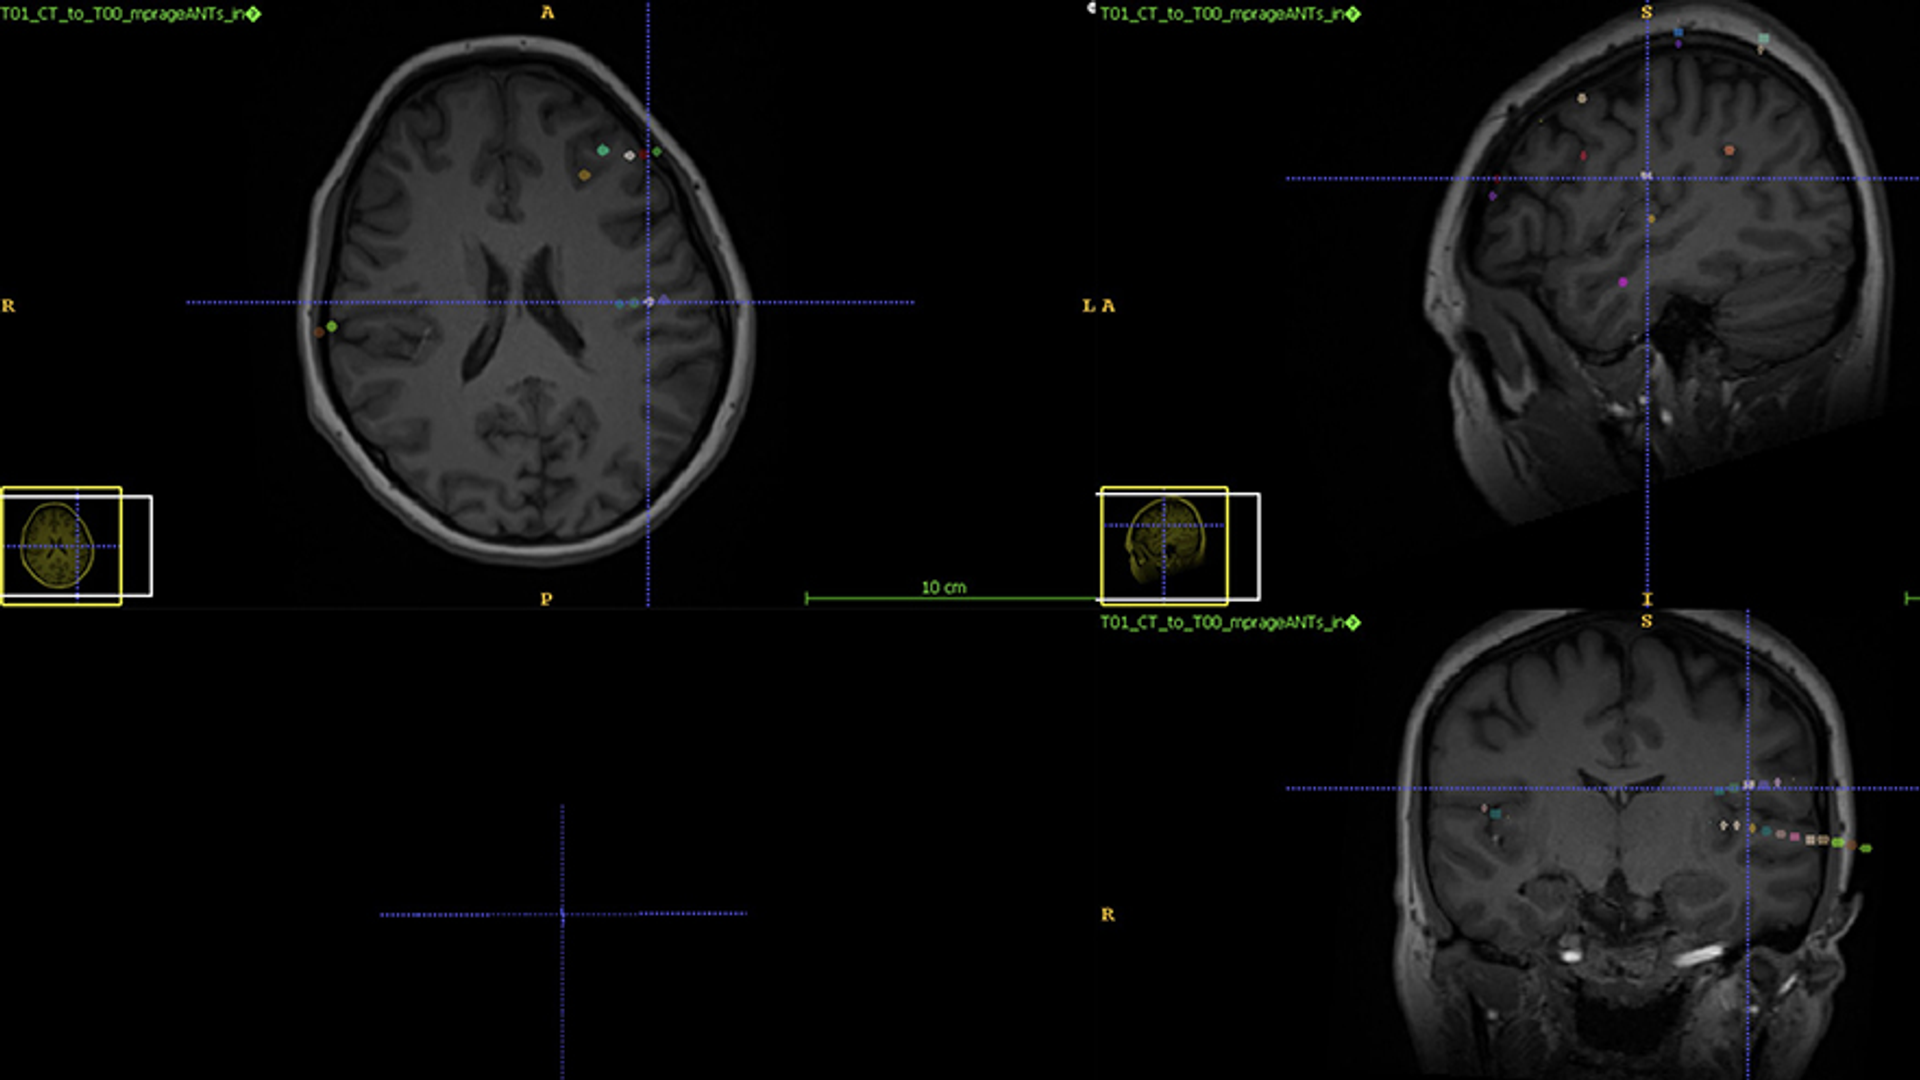

Three months after her LITT procedure, a follow-up MRI exhibited a small, well-defined lesion in the left posterior insula made by the laser (Figure 3). She has been seizure-free in the three years since her procedure and has returned to work.

Brain scans (3) after LITT showing elimination of seizure source

Figure 3: An MRI image showing the location of the laser ablation (arrows) 3 months after the patient’s surgery.